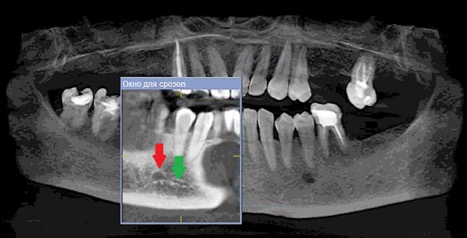

Данные осложнения происходят из-за повреждения резцовой петли – внутрикостного продолжения нижнелуночкого нерва (Рис. 1a и 1b), которая начинается от ментального отверстия и заканчивается индивидуально, как правило, на уровне латерального или центрального резца [1].

Рисунок 1а: КЛКТ. Панорамный реформат.

(Зеленая стрелка – резцовая петля, красная стрелка – подбородочное отверстие.)

На 85 компьютерных томограммах с каждой стороны нами было проанализировано расположение ментального отверстия относительно проекции зубов нижней челюсти (Диаграмма 1).

Диаграмма 1: Расположение ментального отверстия